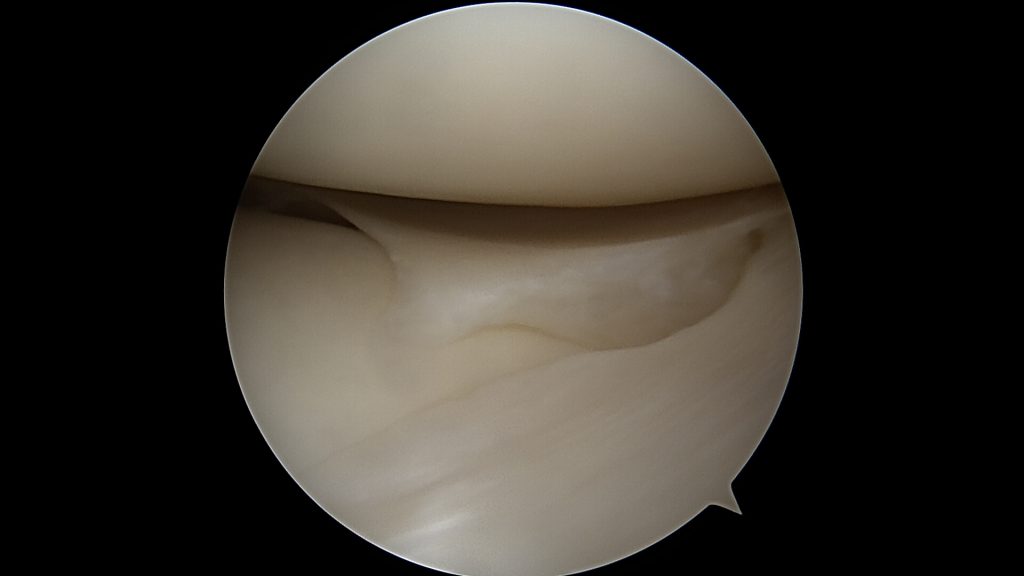

Potwierdzenie rozpoznania tego uszkodzenia następuje podczas zabiegu bardzo szybko. Zaraz po wprowadzeniu optyki do stawu po prostu widzimy łąkotkę nie tam gdzie powinna być, czyli tuż przed kamerą. Po wykonaniu inspekcji wszystkich dostępnych części stawu dokonuje się odświeżenia miejsca uszkodzenia oraz „repozycji” uszkodzonego fragmentu łąkotki (przepchnięcia jej na swoje miejsce). Następnie przy pomocy szwów zakładanych artroskopowo mocują się ją na swoim miejscu.

Po zabiegu wymagane jest unieruchomienie kolana w ortezie na kilka tygodni, odciążanie stawu poprzez stosowanie kul łokciowych a następnie fizjoterapia celem uzyskania pełnego zakresu ruchomości stawu. Ale w tym przypadku zachowujemy praktycznie całą naszą łąkotkę.